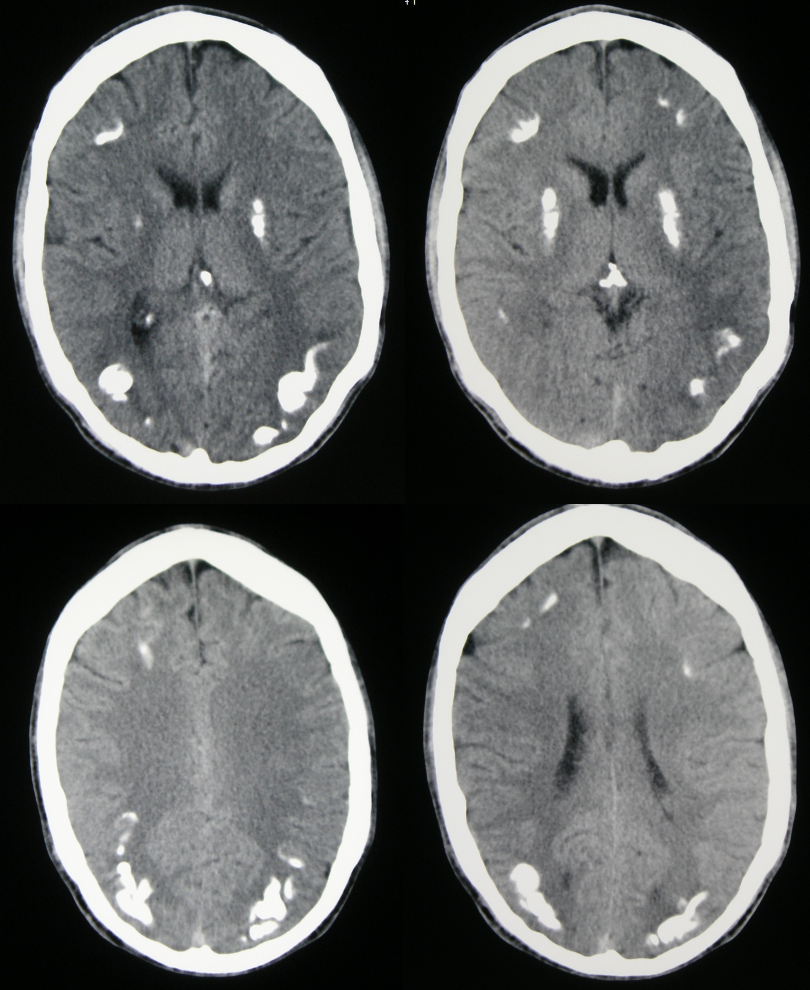

En algunas ocasiones, la causa de estos trastornos es algún fármaco o tóxico al que se ha estado expuesto. En otras, se debe a lesiones estratégicas en el sistema nervioso, ya sea por traumatismos, a consecuencia de un ictus, o de causa neurodegenerativa o genética. En todos los casos, un correcto diagnóstico primero sindrómico, que permita orientar correctamente las pruebas diagnósticas necesarias, y con ellas posteriormente un diagnóstico etiológico (de la causa), nos darán la oportunidad de tomar las medidas adecuadas para curar o, si esto no es posible, aliviar los síntomas y enlentecer la progresión de la enfermedad.